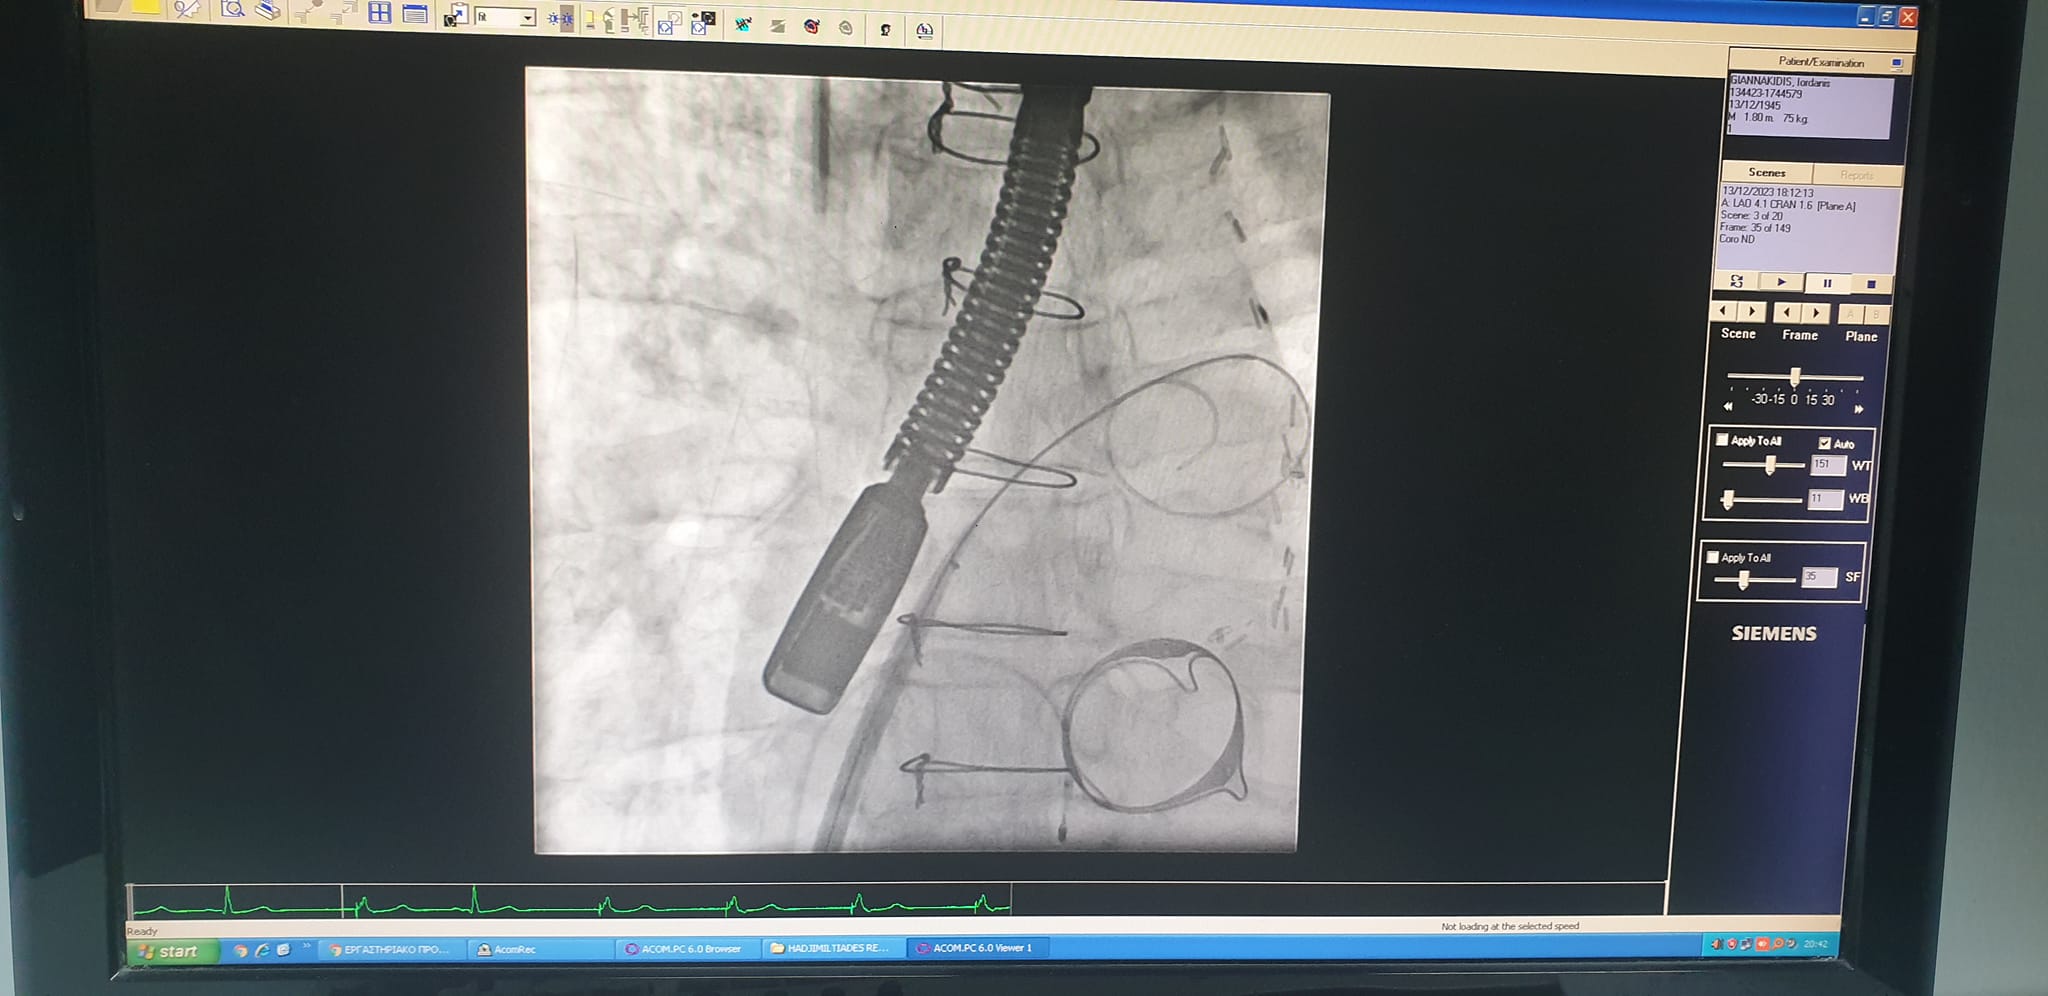

Σχετικά με την ίδια την επέμβαση, έγινε πρόσβαση μέσω της μηριαίας φλέβας του ασθενούς, παρακέντηση του μεσοκολπικού διαφράγματος (atrial septal puncture) με ειδικές βελόνες, διαστολή του με ειδικά μπαλόνια και χρήση εξειδικευμένων καθετήρων και συρμάτων προκειμένου το σύστημα τοποθέτησης της διακαθετηριακής μιτροειδούς βαλβίδας (Myval THV, MERIL) να εισέλθει στον αριστερό κόλπο και από εκεί η νέα βαλβίδα να τοποθετηθεί μέσα στην παλαιά δίνοντας λύση στο πρόβλημα. Η επέμβαση έγινε με γενική αναισθησία υποστηριζόμενη από έμπειρο καρδιοαναισθησιολόγο και καθοδήγηση με διοισοφάγειο υπερηχοκαρδιογράφημα από την έμπειρη ομάδα απεικόνισης της Α’ Καρδιολογικής Κλινικής.